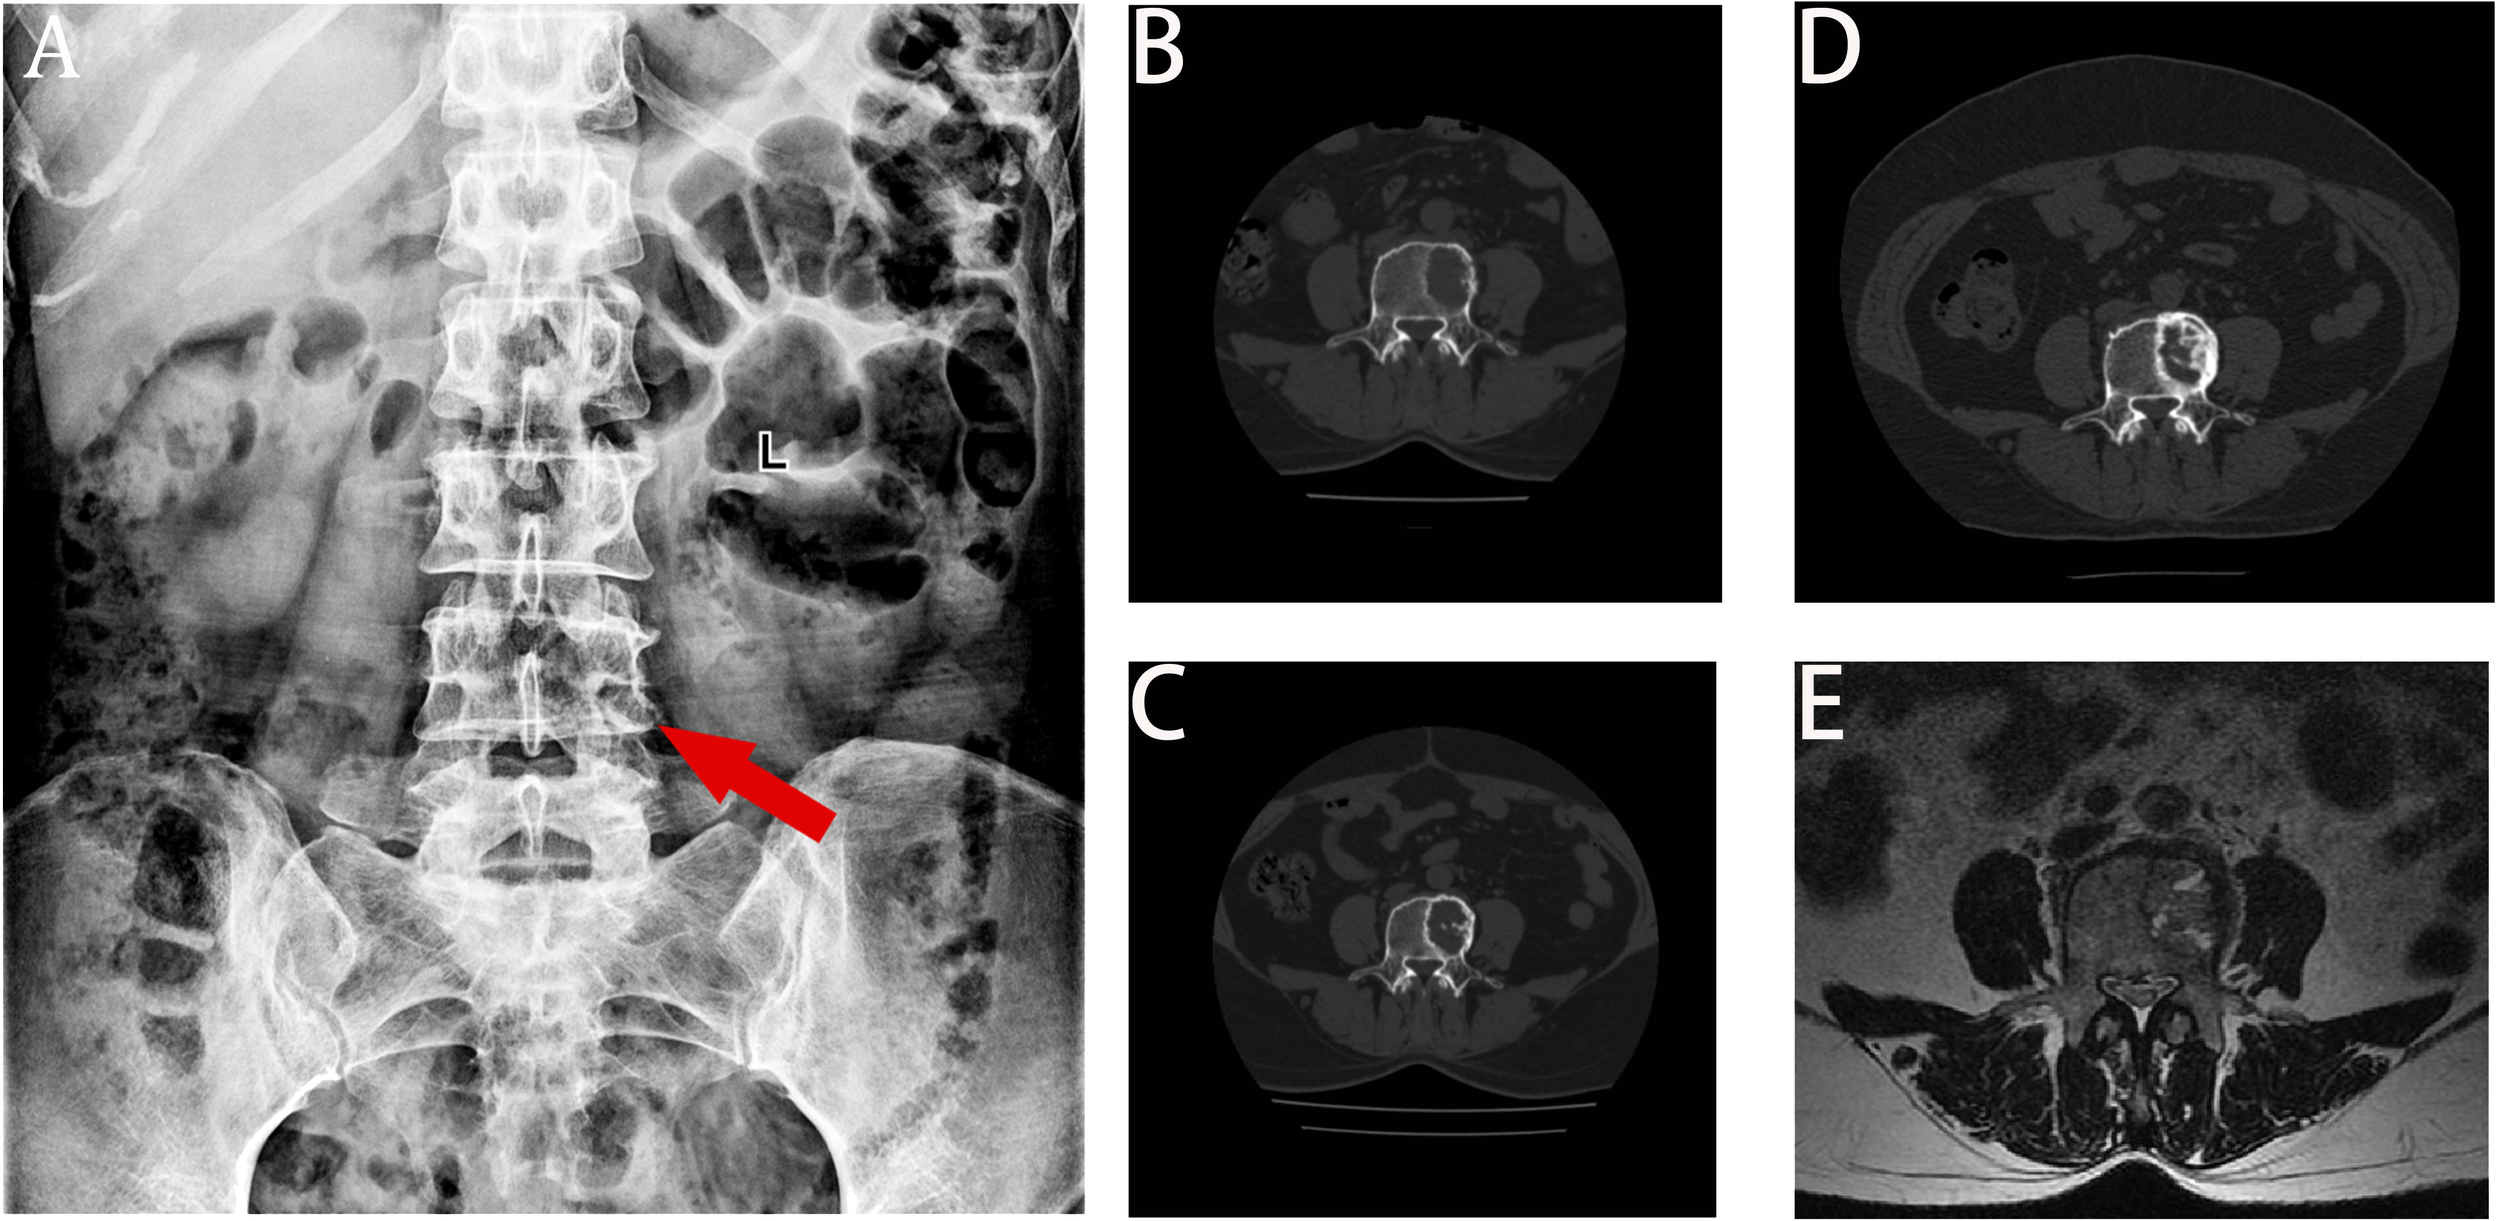

A 68-year-old female patient presented at our hospital on 28 May 2023, with a chief complaint of “low back pain with left lower limb pain for 2 weeks.” Upon specialized physical examination, she exhibited a normal gait upon entering the ward. The patients reported left lumbar back pressure pain without radiation to the lower limb. Examination of the lumbar spine indicated normal flexion and extension activity, with left quadriceps muscle strength graded at level IV. Sensation in the lower limbs and saddle area was intact, alongside normal muscle tension. Bilateral heel–knee tendon reflexes were within normal limits, with no pathological signs detected. Normal skin temperature and color were normal in the right axilla. Palpitation revealed soft masses approximately 5 cm × 3 cm in depth, with indistinct boundaries, absence of tenderness, and immobility. Subsequent lumbar spine X-ray depicted slight flattening of the lumbar vertebra 4 (L4) vertebral body (Figure 1A). Computed tomographic (CT) imaging of the lumbar spine revealed flattening of the L4 vertebral body, thin and discontinuous bone cortex, and osteolytic bone destruction on the left side of the vertebra, measuring approximately 3.0 cm × 2.0 cm × 2.2 cm (Figure 1B). No compression of the dural sac or significant abnormalities in the surrounding soft tissue were noted. Lung CT revealed distinctive insect-like patterns of local bone destruction affecting thoracic vertebra 4 (T4) and the right first rib, with irregular soft tissue density shadows observed in the right armpit (Figure 2B). Lumbar magnetic resonance imaging (MRI) displayed an uneven bone damage signal in the L4 vertebral body (Figure 1E). Ultrasonography detected a low-echo mass measuring approximately 32 mm × 26 mm, featuring clear boundaries and an irregular shape, exhibiting uneven internal echoes and the characteristic “rat tail sign” at both ends in the right axilla (Figure 2A). Emission computed tomography (ECT) scans revealed multiple abnormal focal nuclide concentrations in the right first rib, L4 vertebral body, and right iliac bone, consistent with bone metastases (Figure 3). To determine the nature and origin of the tumors, a CT-guided puncture biopsy of the right iliac bone tumor was conducted on 29 May 2023, revealing a short spindle-cell malignant mesenchymal tumor suggestive of MPNST upon immunohistochemistry and staining (Figure 4A). Subsequently, on 6 June 2023, an ultrasound-guided puncture biopsy of the right axillary soft tissue tumor confirmed MPNST (Figure 4B). The final diagnosis was MPNST with multiple metastases.

Figure 1

X-ray, CT, and MRI images. Panel (A) displays the flattening of the L4 left vertebral body height. Panel (B) displays the bone destruction of L4 before chemotherapy, with a moderately circular low-density shadow with a range of 3.4 cm × 2.0 cm × 2.2 cm. Panel (C) displays a decrease in lytic bone destruction and an increase in the cortical bone density in posterior L4 after six cycles of chemotherapy. Panel (D) displays obvious calcification in the bone destruction area of the L4 vertebra at the last review. Panel (E) displays that the left side of the L4 vertebra is slightly flattened, with patchy long T1 equal length T2 signals and high T2 pressure lipid images.

Following thorough departmental deliberation, initiation of a chemotherapy regimen combining cisplatin with doxorubicin was decided upon. Given the predominant imaging findings of osteolytic bone destruction, denosumab, FDA-approved for preventing skeletal-related events in patients with bone metastasis from solid tumors, was adjunctively administered to inhibit osteolysis. The treatment protocol combined chemotherapy (AP regimen cisplatin (DDP) 120mg/m2/day ×1 day + pegylated liposomal doxorubicin (PLD) 40 mg/m2/day × 1 day, once every 21 days) with denosumab (120 mg, subcutaneous injection, once/4 weeks), supplemented with Vitamin D3 (600 μg daily). Throughout the treatment course, the patient experienced significant alleviation of pain symptoms compared to admission, improved sleep without medication assistance, and absence of drug-related adverse reactions. Regular imaging assessments performed before each admission facilitated the evaluation of the combination therapy’s efficacy. Following the completion of six cycles of chemotherapy, pulmonary CT scans evidenced a gradual reduction in the maximum diameter of the irregular soft tissue mass under the right axilla (Figure 2C), while lumbar spine CT exhibited thickening and densification of the bone cortex surrounding the L4 vertebral body, accompanied by evident bone formation and scattered calcification shadows in the area of osteolytic bone destruction (Figure 1C).

On 18 October 2023, the patient completed six cycles of chemotherapy combined with denosumab treatment, with lung CT indicating an absence of lung metastasis. Evaluation of the soft tissue mass in the right armpit, designated as the target lesion according to RECIST 1.1 criteria, revealed stable disease. To inhibit disease progression post-cessation of intensive chemotherapy cycles, the patient was prescribed the oral targeted drug anlotinib (12 mg/day, taken for 2 weeks followed by a 1-week break) to enhance chemotherapy sensitization and prevent disease progression. Denosumab (120 mg, subcutaneous injection, once every 4 weeks) was continued to enhance bone strength. Presently, the patient has endured the tumor for 10 months. Regular follow-up visits every 3 months for lung and lumbar CT scans were advised to monitor therapeutic efficacy and adjust the medication regimen as necessary. On 20 February 2024, a re-examination CT revealed prominent calcification in the area of bone destruction in the L4 vertebral body (Figure 1D), with no significant alteration in the maximum diameter of the axillary mass compared to the previous scan (Figure 2D).